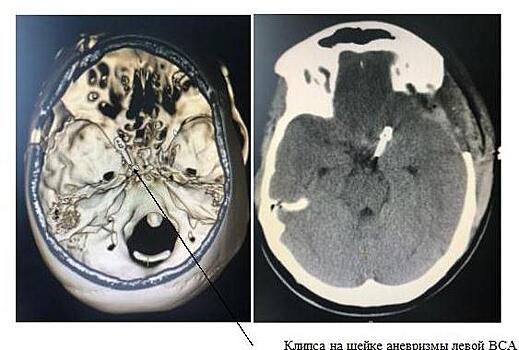

Нейрохирурги больницы Вересаева Департамента здравоохранения Москвы спасли 21-летнюю пациентку с разрывом аневризмы внутренней сонной артерии. В больницу имени Вересаева бригада скорой помощи доставила 21-летнюю пациентку. Больная жаловалась на головную боль после обморока. По неврологической симптоматике врачи предположили инфаркт головного мозга, но не могли исключить и дебют рассеянного склероза. При проведении КТ- обследования подтвердился инфаркт головного мозга в бассейне правой передней мозговой артерии. Инфаркт головного мозга возник у больной на фоне кажущегося полного здоровья: артериальное давление в норме, патологий сердечно-сосудистой системы не выявлено, никаких препаратов пациентка не принимала. Это заставило неврологов и нейрохирургов искать причину недуга более детально и провести дополнительное обследование - КТ ангиографию сосудов головного мозга с контрастным веществом, которое и выявило аномалию – аневризму в области развилки левой внутренней сонной артерии. Специалистами было заподозрено, что тяжелое состояние, в котором девушка поступила в больницу, было вызвано субрахноидальным кровоизлиянием. Пациентка к счастью пережила его в первый раз без больших неврологических последствий. Но патологическое выпячивание стенки сосуда могло разорваться в любой момент, что могло привести к тяжелым последствиям и даже к летальному исходу. Пациентку стали готовить к операции. Через два дня у пациентки внезапно произошло ухудшение состояния: сильная головная боль, неоднократная рвота. По экстренным показаниям выполнено МСКТ головного мозга, выявлено повторное массивное кровоизлияние в субарахноидальное пространство (полость между паутинной и мягкой мозговыми оболочками) - аневризма неожиданно лопнула. Срочно в воскресный день вызвана операционная бригада: профессор кафедры нейрохирургии и нейрореанимации МГМСУ им. Евдокимова Владимир Дашьян, заведующий нейрохирургическим отделением Евгений Сосновский, анестезиолог Денис Марченко. Девушке выполнили сложное нейрохирургическое вмешательство с применением интраоперационного микроскопа – костно-пластическую трепанацию черепа в левой лобно-височно области, затем на патологический участок сосуда наложили специальную клипсу. Операция прошла успешно, кровотечение было остановлено. В послеоперационном периоде пациентка полностью восстановилась, неврологический дефицит отсутствовал. Выписана домой на амбулаторное наблюдение. Вовремя выявленная специалистами опасная патология сосудов головного мозга и успешно выполненная экстренная операция позволили не только спасти жизнь молодой пациентки, но и полностью восстановить ее жизненную активность.